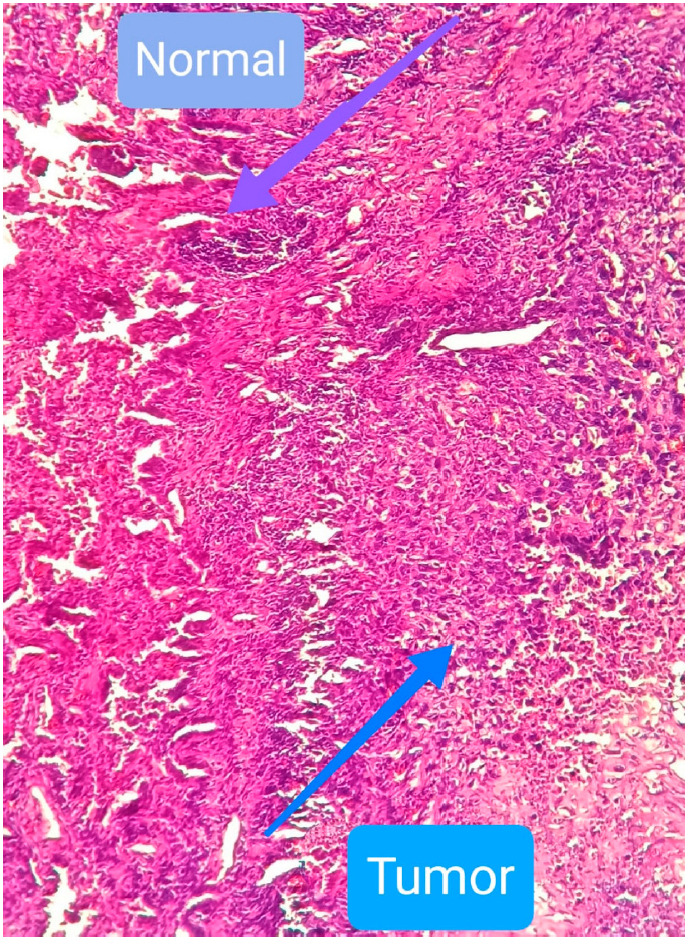

肺、乳腺和结肠组织的正常细胞和癌细胞的质膜显示出相当不同的脂质成分,这在很大程度上影响了它们的理化性质。通过 EPR 光谱评估了自旋探针 2,2,6,6-四甲基哌啶-1-氧(TEMPO)在人类肺部正常细胞和癌细胞膜中的分配情况,以估计脂质成分的影响。目的是揭示可归因于膜特性的潜在癌症治疗策略。研究在 pH 值分别为 7.3 和 6.2 的条件下进行,这与正常细胞和癌细胞的微环境相关。在 283-317K 的温度区间内检测了 TEMPO 的分配,以揭示化疗中使用的局部热疗的功效。结果表明,人肺癌细胞膜的 TEMPO 分配系数明显高于邻近的正常细胞膜。在相对较高的温度下,正常细胞和癌细胞的分配系数都有所提高。不过,与正常细胞相比,癌细胞在所研究的温度范围内表现出更高的分配系数。使用 C12SL(月桂酸的自旋标记类似物)获得的数据表明,癌细胞膜动力学的增强可能是 TEMPO 分配增强的一个机制。在 pH 值为 6.2 和 7.3 时估算的分配自由能值表明,在 pH 值为 7.3 时,癌细胞中 TEMPO 分配所需的能量减少了 30%。TEMPO 及其衍生物曾被视为癌症研究中的治疗剂。数据表明,TEMPO 衍生物可用于测试补充碱化疗法对接受标准化疗和局部热疗的癌症患者是否有效。

The plasma membranes of normal and cancer cells of the lung, breast, and colon tissues show considerably different lipid compositions that greatly influence their physicochemical properties. Partitioning of the spin probe 2,2,6,6-tetramethylpiperidine-1-oxyl (TEMPO) into the membranes of human lung normal and carcinoma cells was assessed by EPR spectroscopy to estimate the impact of the lipid compositions. The goal was to reveal potential strategies for cancer therapy attributable to the membrane properties. The study was conducted at pH values of 7.3 and 6.2, relevant to the microenvironments of normal and cancer cells, respectively. The TEMPO partitioning was examined in the temperature interval of 283-317K to reveal the efficacy of local hyperthermia used in chemotherapy. Results indicate that the TEMPO partitioning coefficient for the membranes of human lung carcinoma cells is significantly higher compared with that of neighboring normal cells. Increased partition coefficients were observed at relatively higher temperatures in both normal and cancer cells. However, compared to the normal cells, the cancer cells demonstrated higher partition coefficients in the studied temperature range. The data obtained with C12SL (spin-labeled analog of lauric acid) indicate that increased membrane dynamics of the cancer cells is a possible mechanism for enhanced partitioning of TEMPO. Free energy values for partitioning estimated for pH values of 6.2 and 7.3 show that TEMPO partitioning requires 30% less energy in the cancer cells at pH 7.3. TEMPO and its derivatives have previously been considered as theranostic agents in cancer research. Data suggest that TEMPO derivatives could be used to test if complementary alkalization therapy is effective for cancer patients receiving standard chemotherapy with local hyperthermia.